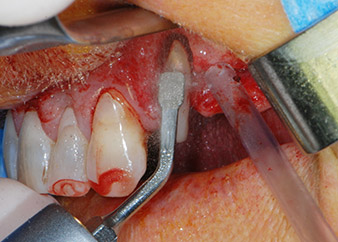

Las deficiencias óseas alrededor de los implantes, en el área mesial de la pieza 27 y alrededor de la raíz bucal de la pieza 24, se obturaron con partículas sustitutas de hueso xenógeno (Geistlich Bio-Oss) y se cubrieron con una membrana de colágeno absorbible (Geistlich Bio-Gide) a efectos de realizar un aumento mediante GBR

(figuras 13 y 14).

Fig. 13: Se utilizó material sustituto de hueso xenógeno para obturar los defectos óseos residuales, ...

membrana de colágeno absorbible

Fig. 14: ... ... que después se cubrió con una membrana de colágeno absorbible. La estructura grisácea y rosa que se ve entre los elevadores del margen superior de la imagen representa el tejido papilar interproximal.